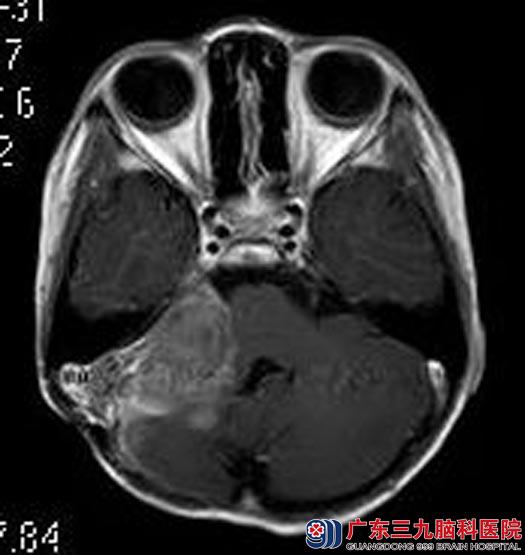

佳佳今年9岁,一个月突然出现了头痛,伴有恶心、呕吐,四肢抽搐三次。当地医院头颅CT检查提示右侧小脑半球占位。广东三九脑科医院进一步头颅MRI检查,结果提示:右侧桥小脑角区示一较大的团块状占位性病变,大小约4.05cm×2.96cm×3.69cm,小脑天幕强化,以右侧明显,脑干及四脑室稍受压,考虑髓母细胞瘤可能性大。